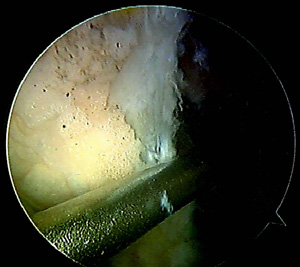

Adoptamos ésta técnica desde el 2007, en más de 500 reconstrucciones realizadas no hemos tenido incidentes ni complicaciones en la creación del túnel o en la fijación femoral. En un estudio recién concluido en 90 pacientes divididos en dos grupos y en donde evaluamos la colocación del túnel femoral utilizando con TAC-3D, uno con la técnica transtibial convencional y en el segundo, la descripta en éste artículo; encontramos que en el grupo transtibial se logró la colocación anatómica del túnel femoral en 43% de los casos, mientras que el grupo de PAM en el 98% de los casos (Fig 6).

Figura 6: TAC-3D donde se observa la colocación anatómica

del túnel femoral en un caso operado con la técnica

del portal anteromedial.